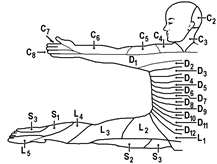

Ноцицептивная стимуляция внутреннего органа часто вызывает ощущение боли не в нем самом, а в отдаленных, поверхностных частях тела, или не только в нем самом, а также в отдаленных частях тела. Такая боль называется отраженной. Как правило, она охватывает участки периферии, иннервируемые тем же сегментом спинного мозга, что и затронутый внутренний орган. Иными словами, на поверхности кожи боль проявляется в соответствующем дерматоме (рис.).

Вспомним! Дерматом – ограниченная область кожи, которую иннервирует афференты одного заднего корешка. В скелетной мускулатуре эквивалентами дерматомов являются миотомы.

Рис.. Дерматомы. Вид спереди.